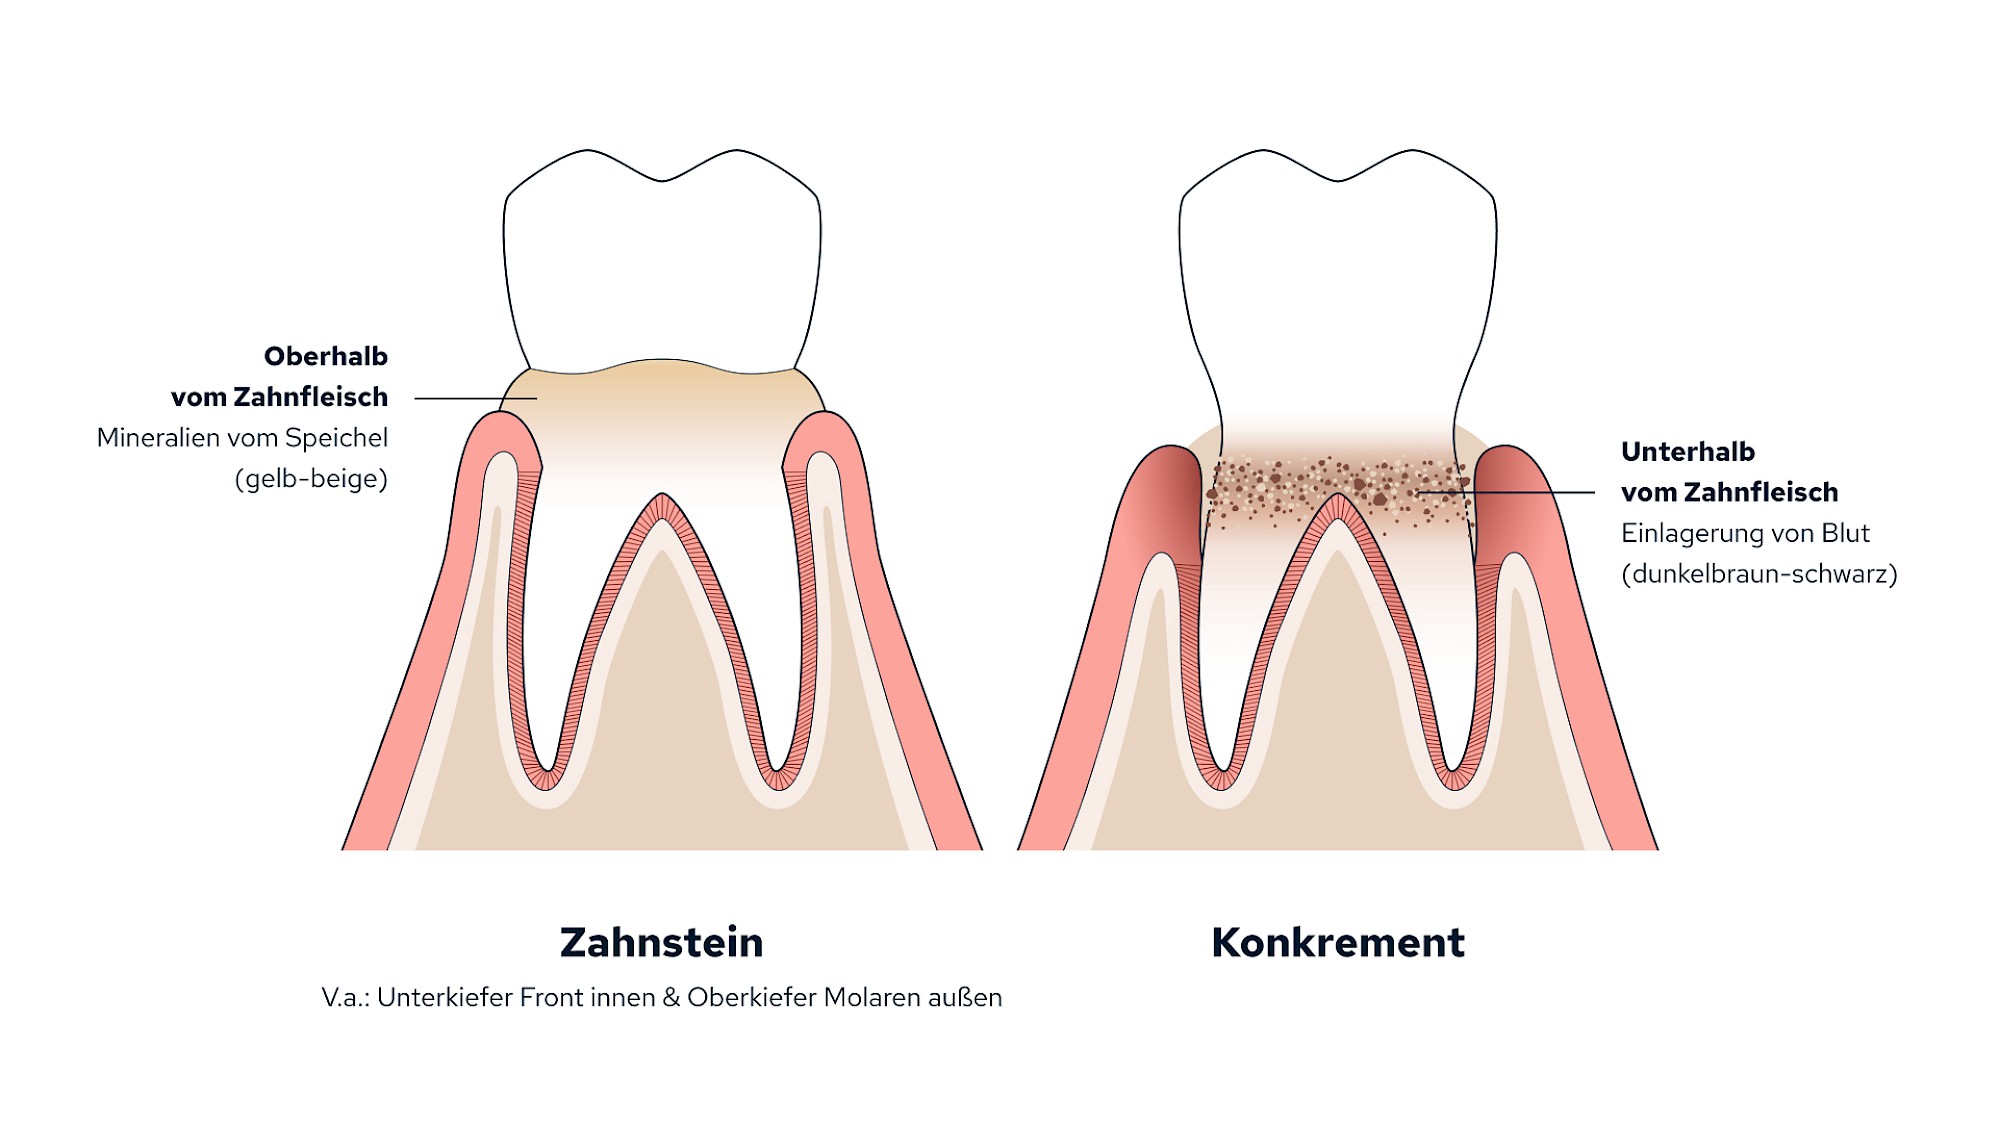

Zahnstein

Lagern sich Mineralien wie Calcium und Phosphat aus dem Speichel in den Zahnbelag ein, so bildet sich oberhalb vom Zahnfleisch gelb-beiger harter Zahnstein. Zahnstein kann nicht mit der Zahnbürste weggeputzt werden und erschwert die Mundhygiene zusätzlich.

Vor allem dort, wo große Speicheldrüsen den Speichel in die Mundhöhle entlassen, bildet sich besonders schnell Zahnstein:

- An den Außenflächen der Oberkiefer-Molaren (Backenzähnen)

- An den Innenflächen der Unterkiefer-Frontzähne

Konkrement

Von Konkrement spricht man, wenn gleichzeitig der Zahnhalteapparat entzündet ist und sich der Knochen um die Zähne zurückgebildet hat. In diesen Fällen kann sich Zahnstein auch unterhalb vom Zahnfleisch in den Zahnfleischtaschen bilden. Die dunkelbraun-schwarze Färbung stammt aus dem entzündlichen Taschensekret und der Einlagerung von Blutbestandteilen.

Sowohl Zahnstein als auch Konkrement kann nur der Zahnarzt entfernen.

Unterscheidung von Zahnstein und Konkrement

Unterscheidung von Zahnstein und Konkrement